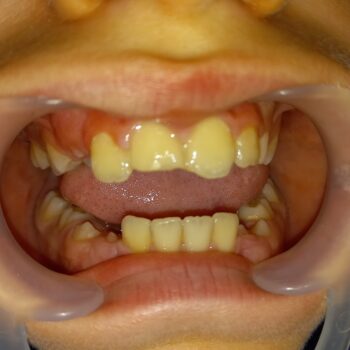

• Ολική αποκατάσταση παιδικού στόματος